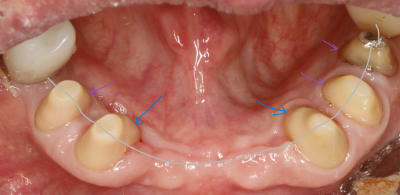

ici , on doit faire un bridge canine canine .les autres dents sont juste des piliers accessoires .

dejà , le bridge canine +accessoires par sa forme de fer à cheval est auto stable puisque les forces principales viennent d en haut et de devant .

les canines etant les plus costaudes , on va donc essayer de ne pas trop les fracasser et les choisir comme axe d insertion . ce sera donc notre axe de taille directeur . cet axe etant bien sur l axe moyen (ou commun) entre les deux .

donc on commence par tailler les canines en mettant de dépouille .

devant ( en vestibulaire ) on a vu que c etait auto stable , à condition bien sur de laisser la place au montage des dents . donc la courbure de devant dépend de la forme cingulaire des dents du haut .eh oui :-)

là on a pas encore parlé de congés ou quoi que ce soit .

alors maintenant derrière c est diffèrent , avec la langue , ce n est pas du tout auto stable , et vu que devant c est assez incliné , il va falloir trouver de la rétention . et y en a pas beaucoup et elle se trouve juste au depart de la dent . elle est si précieuse qu une fois taillée , on y reviendra plus jamais .

ce sera notre axe de rétention de référence pour tout le bridge .

et on ne peut pas dire qu il y ait de la conicité entre les deux .

voir les traits bleus sur la photo , sauf si comme dans mission impossible , elle disparait .:-)

arrive maintenant le congé .

on a vu qu en vest , du fait que ce soit penché à cause des dents du haut , ce serait bien de rajouter une opposition avec la face linguale .

donc au pied si on pouvait rentrer un peu tout en redressant ce serait pas mal .

ben voilà , il sert à ca le congé , le voilà . à faire la férule de PP :-)

en plus ca fait plaisir au labo qui va pouvoir s amuser dessus à faire l artiste .

le congé doit donc servir à réduire la conicité .

c est pour ca qu il doit être fait APRES la face linguale .

puisque que peuchère , la face linguale étant limitée , on s adapte à elle et on parallélise à mort , enfin on essaye .

traits rouges sur photos .

bon maintenant on va s occuper des autres .

les autres , accessoires , faut qu elles suivent le mouv s agirait pas quelles n en face qu à leurs tête . .

elles sont là pour s intégrer au bridge et si possible en augmentant la stabilisation .

ce qui veut dire qu il ne faudrait pas quelles soit plus ou moins rétentives que les canines .

il ne s agirait pas :

qu elles créent un point de rotation en étant plus rétentives

ou bien qu elles soient moins rétentives auxquelles cas elles ne serviraient à rien .

oui pcq c est le plus fort qui prime à ce jeu là donc le mieux c est tous pour un , le bridge unificateur .

et pour cause c est un bridge de contention .

deja qu elles tiennent par miracle , autant qu elles ne nous emmerdent pas , surtout si si on risque de les perdre un jour .

donc on les parallélise aux canines sur les faces vest .

traits verts sur photo